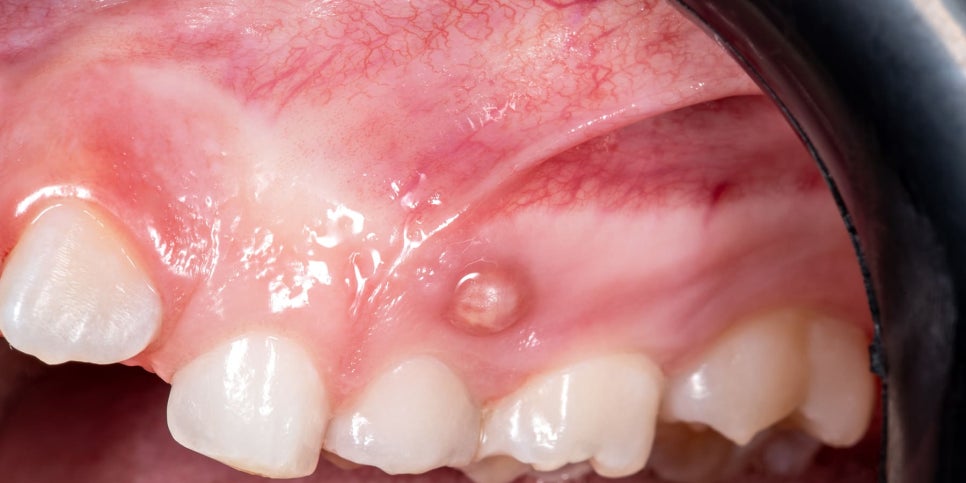

위 사진을 보세요. 잇몸에 여드름처럼 볼록 튀어나와있습니다. 안쪽에는 고름이 차있는데요, 치아 끝 뿌리쪽에서 생긴 염증이 형성되어 공간이 없어 잇몸쪽으로 빠져나가는 현상때문에 발생합니다.(출처: https://youngdentalsf.com)